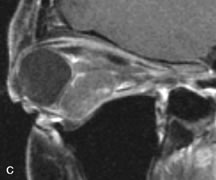

Extraocular muscle enlargement in patients with thyroid-associated orbitopathy is demonstrated equally well with CT and MRI studies. However, the superior tissue contrast on MR images reveals better details of the relationships of the optic nerve to the thickened muscles at the orbital apex (Fig. 16).50 In addition, MRI may be able to differentiate between muscles that are enlarged as a result of edema and active inflammation and those enlarged because of fibrosis by their T2 relaxation times.21 Quantitative MRI was not found to be accurate in predicting the success of low-dose orbital irradiation.51 However, a muscular index relating the diameters of the rectus muscles to the bony orbital dimensions was useful in predicting optic nerve compression.52

Fig. 16. A-C, T1-weighted MR scans obtained with a high-resolution surface coil demonstrate fusiform enlargement of the extraocular muscles. The medial, lateral, and inferior rectus muscles are especially involved. Note the relative sparing of the tendinous insertions, a finding characteristic of this disease process, as well as fatty infiltration of the lateral and inferior rectus muscles. There is marked proptosis, best visualized on the sagittal image (A), and mild crowding of the optic nerve at the orbital apex.